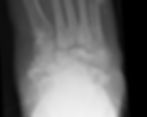

Charcot foot stage III

Eichenholtz Stages

0 – Joint oedema, no x-rays changes

1 – Joint oedema, osteopenia, periarticular fragmentation, dislocation (Fragmentation)

2 – Decreased oedema, coalescence, absorption of fine bony fragments, fusion and early sclerosis (Coalescence)

3 – No oedema, more stable and deformed foot because of reconstruction and remodelling changes, osteohpytes, subchondral sclerosis and narrowing of joint spaces (Consolidation)

Haematological investigations include CRP, ESR and FBC. Plain radiographs initially may be normal or may show only subtle changes, however in advanced stages more prominent bony destructions and subluxations become evident.